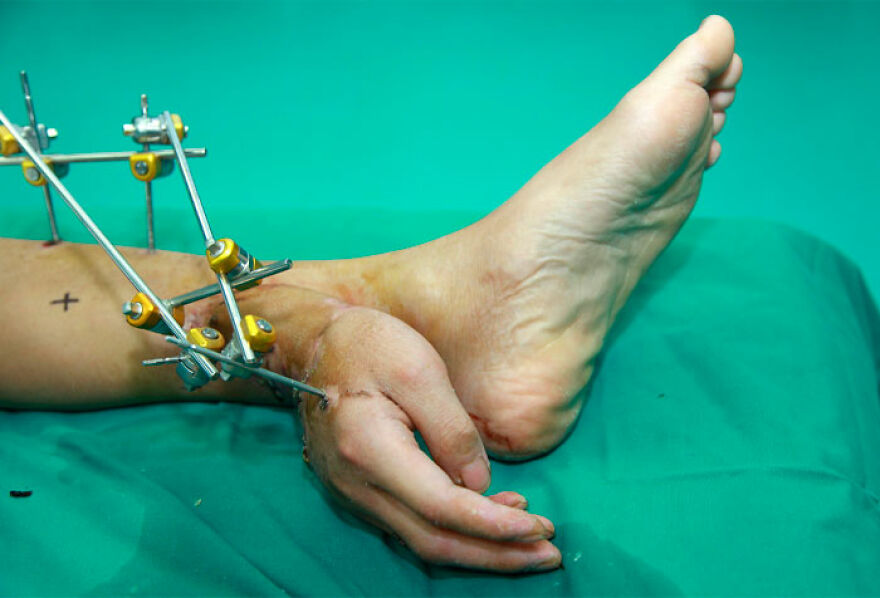

Man's severed hand attached to his ankle to keep it alive until the arm is healed enough for reattachment